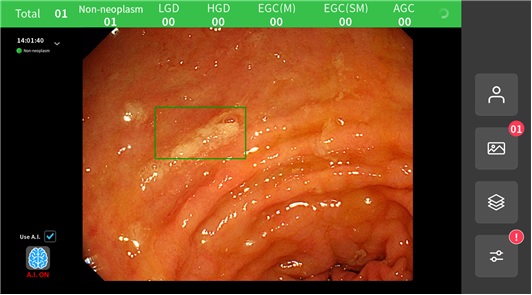

아이도트는 한림대춘천성심병원 소화기내과 방창석 교수팀과 함께 해당 솔루션을 개발했으며, 위내시경 사진들을 6개 중증도(▲Non-neoplasm ▲LGD ▲HGD ▲EGC(M) ▲EGC(SM) ▲AGC) 카테고리별로 분류해준다고 밝혔다. 또한 자체 임상평가 결과, 중증도별 민감도·특이도를 반영한 전체 민감도와 특이도는 각각 91.48%와 92.13%를 확보했다.

아이도트는 해당 솔루션을 활용하여 진료의가 시술 현장에서 즉각적인 도움을 받을 수 있다고 설명했다. 위내시경 시술 중 실시간 동영상을 기반으로 의심 병변 위치를 즉각 표시해줌으로써 진단 보조 시스템의 역할을 할 수 있다는 것.